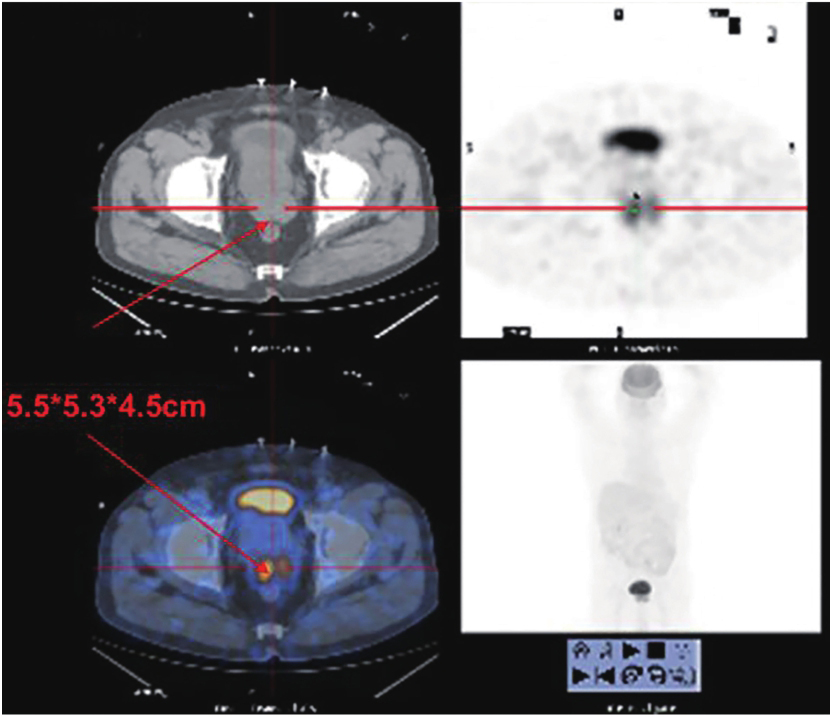

PET-CT:直肠肿物,大小约5.5cm(图1)。

图1 初诊GIST时PET-CT结果